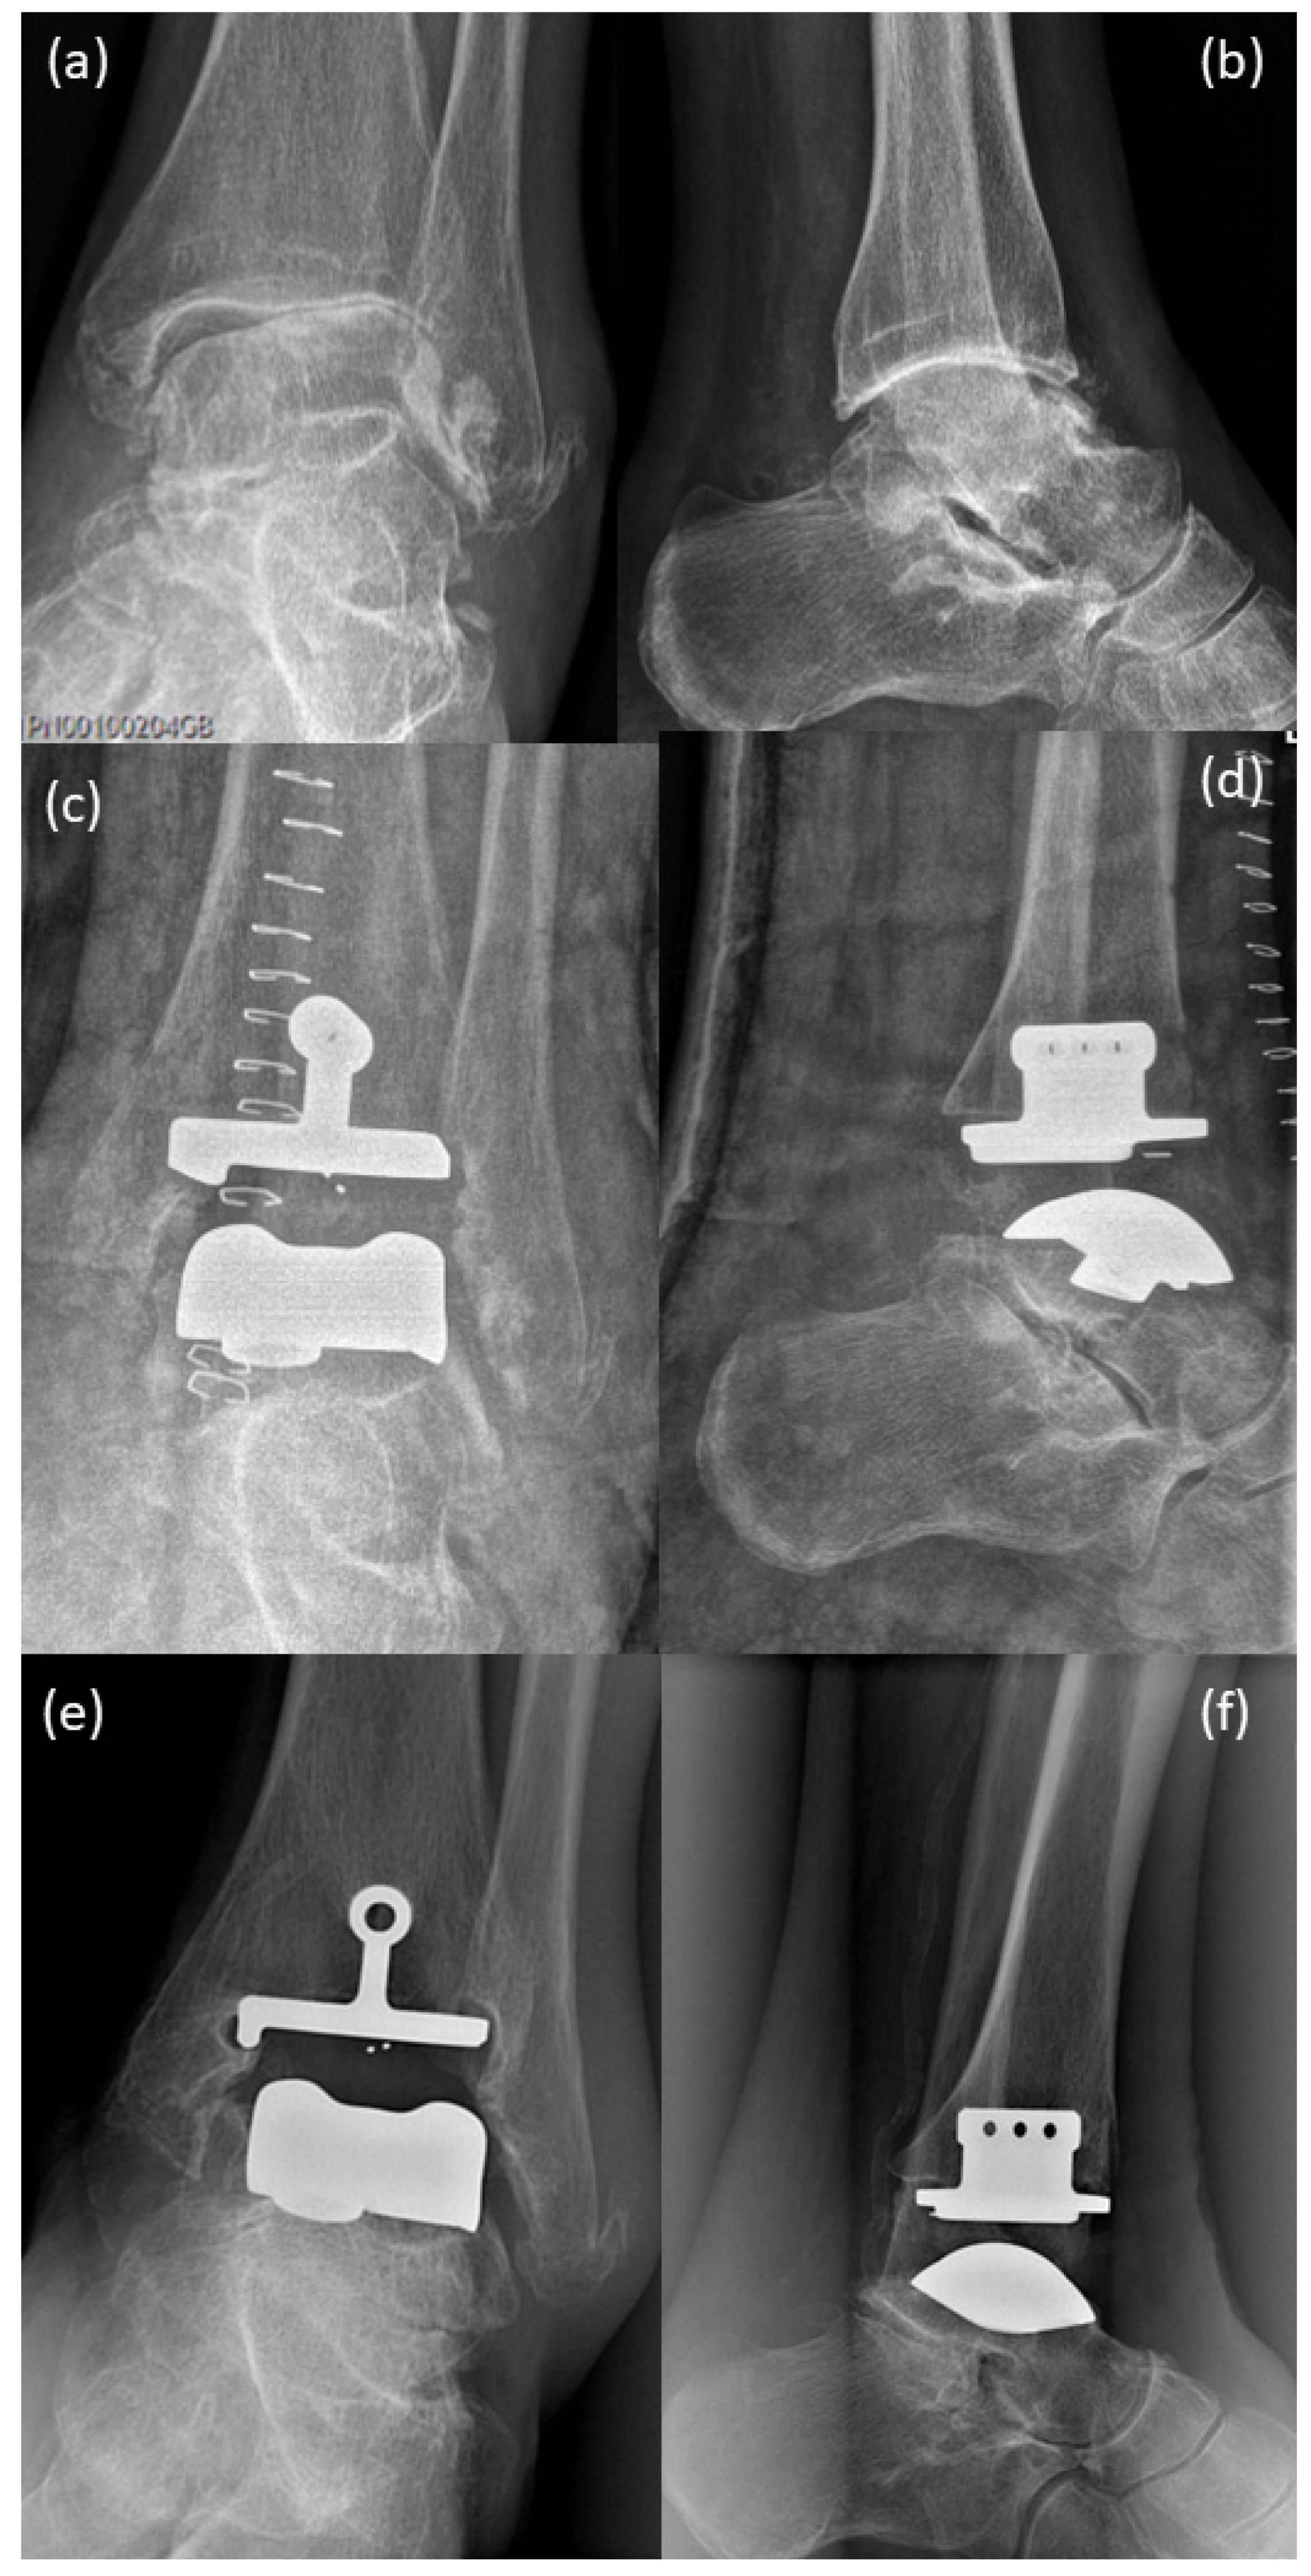

Figure 1.

X-rays: (a,b) before implantation of Salto-prosthesis, pre-OP 2005; X-rays show severe osteoarthrosis of the upper ankle with deformity of joint endplates, osteophyte formation and subchondral sclerosis, as well as periarticular calcifications; (c,d) post-surgical 2006, implanted Salto-prosthesis; with regular post-surgical status; (e,f) X-ray at a routine control performed in 2016 demonstrated beginning of bone resorption and lytic–cystic defects in the periphery of the tibial component while still regularly around the stem of the prosthesis and the talar component.

Because of an old ligament tear on the left upper ankle (1970) and because of severe pain since 1992 under nonsteroidal anti-inflammatory drugs daily, his walking distance was max. 1 h. The X-ray images show severe osteoarthrosis of the upper ankle with deformity of the joint endplates, osteophyte formation and subchondral sclerosis, as well as periarticular calcifications (Figure 1a,b, 2005). Dorsiflexion of the left ankle was 20-0-20 (2006), lateral ligament stable, marked crepitation and marked drawer in the upper ankle joint, pronounced swelling. In 2006, he underwent surgery to implant an upper ankle joint prosthesis. Post-surgery images (2006, Figure 1c,d) show implanted Salto-prosthesis (Tornier GmbH, Burscheid, Germany) with regular post-surgical status. The prosthesis was a first-generation prosthesis (two components). This first-generation prosthesis showed disappointing results over the long term [14].

X-ray of a routine control performed in 2016 (Figure 1e,f) demonstrated the beginning of bone resorption and lytic–cystic defects in the periphery of the tibial component while still regularly around the stem of the prosthesis and the talar component. The patient already suffered pain at this time.